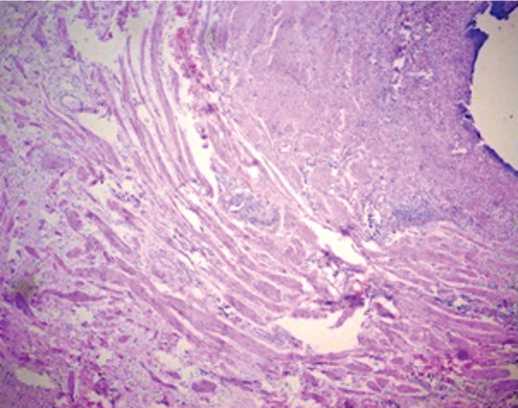

(вне зоны стеноза) нормальная морфологическая картина с организованной мышечной оболочкой,с «неправильным звездчатым» просветом (рис. 2). При

Рис. 2. Срез мочеточника («вне зоны стеноза»), окраска гематоксилином и эозином; увеличение х 200

Fig. 2. Ureter section («outside the stenosis zone»), H&E; x 200

этом отмечены меньшие размеры всей стенки мочеточника (0,42 ± 0,03 мм) и мышечной оболочки (206,52 ± 26,72 мкм) в зоне стриктуры по сравнению с неизмененным отделом мочеточника, толщина стенки мм/мышечной оболочки, мкм – 0,6 ± 0,07 / 420,57 ± отличалась в сторону увеличения органа, со средними значениями – 1,33 ± 0,08 мм, так и в непораженных отделах мочеточника – 1,35 ± 0,08 мм. Указанные изменения отмечены преимущественно за счет мышечной оболочки, где определялась гипертрофия, слабовыра-женные явления воспаления с развитием отека межуточной ткани всех оболочек, также определялась артериальная гиперемия с увеличением количества и наполнения кровеносных сосудов (рис. 5).